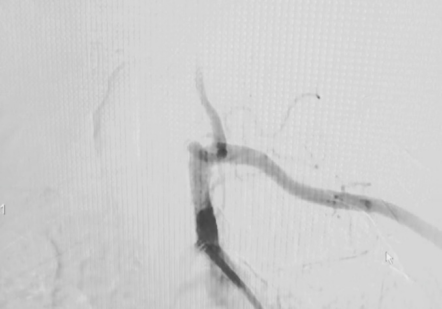

最终造影,验证通畅:

wuwei